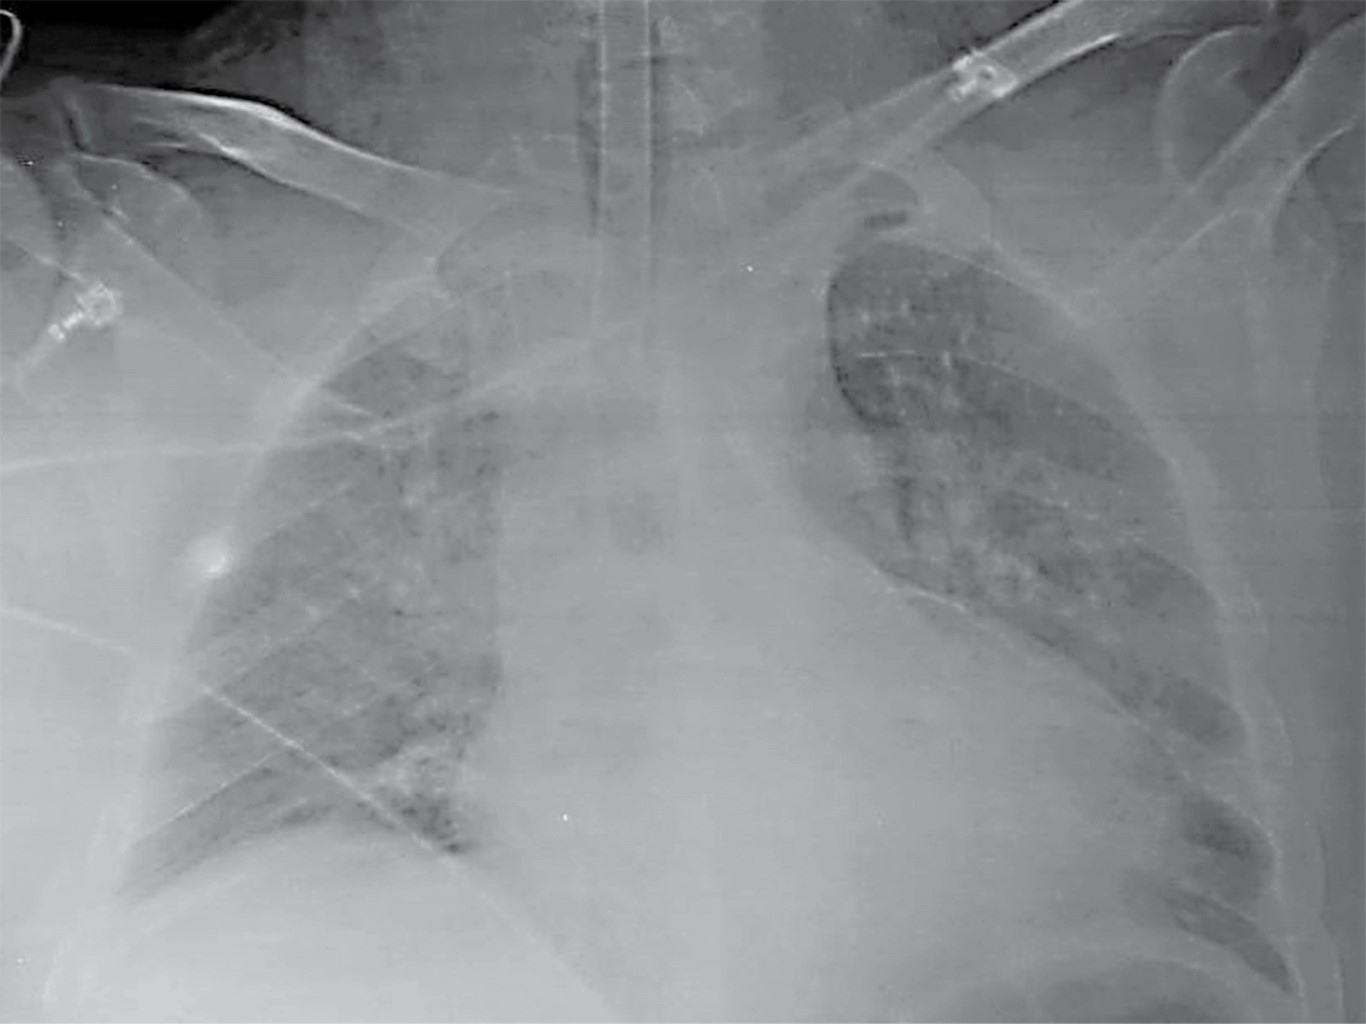

Trombosis coronaria multivaso y ruptura septal interventricular postinfarto de miocardio con elevación del ST, presentación inusual

La trombosis multivaso es un hallazgo poco común en la angiografía coronaria. La ruptura septal ventricular es una complicación mecánica con alta mortalidad en el infarto agudo de miocardio, siendo necesario un tratamiento invasivo de emergencia. La asociación de estas entidades no ha sido reportada en la literatura médica. Este artículo presenta el caso clínico de un paciente con infarto agudo de miocardio sometido a trombólisis, coronariografía, intervención coronaria percutánea y cirugía de urgencia por trombosis coronaria simultánea de descendente anterior y coronaria derecha con rotura interventricular, choque cardiogénico refractario y muerte.

Figura 2

Figura 3

Figura 4

Figura 5

Figura 6